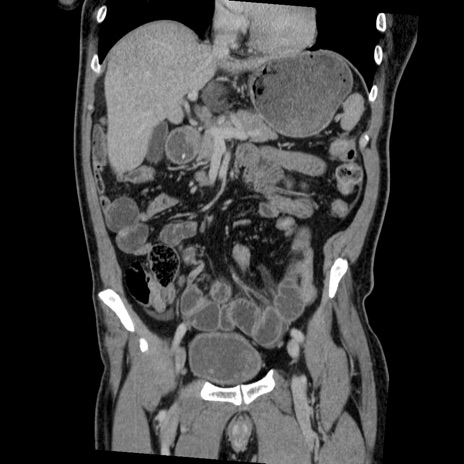

症例22(冠状断像)

【症例】50歳代男性

【主訴】腹痛

【現病歴】AVMからの被殻出血のため回復期リハ病棟入院中。 本日午後3時頃急に下腹部痛が出現した。

【既往歴】AVM、被殻出血、虫垂炎、高血圧

【身体所見】意識晴明、左半身不全麻痺、会話の理解は良好、36.5°C、腹部:膨隆、全体に板状硬、下腹部正中に圧痛点あり、反跳痛-、筋性防御不明、右下腹部にope scar

【データ】WBC 9400、CRP 0.06